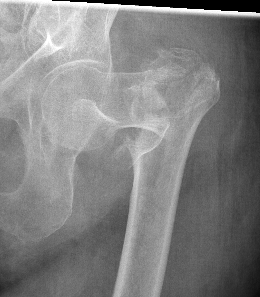

Evans Classification

Two main types

- Type 1 Intertrochanteric

- Type 2 Reverse Oblique

Type 1 Intertrochanteric

2 part undisplaced

2 part displaced

3 part without posterolateral support (GT fracture)

3 part without posteromedial support (LT fracture)

4 part without posterolateral or posteromedial support

Type II Reverse Oblique Type

Inherently unstable - tendency of femoral shaft fragment to shift medially

Reverse oblique fractures